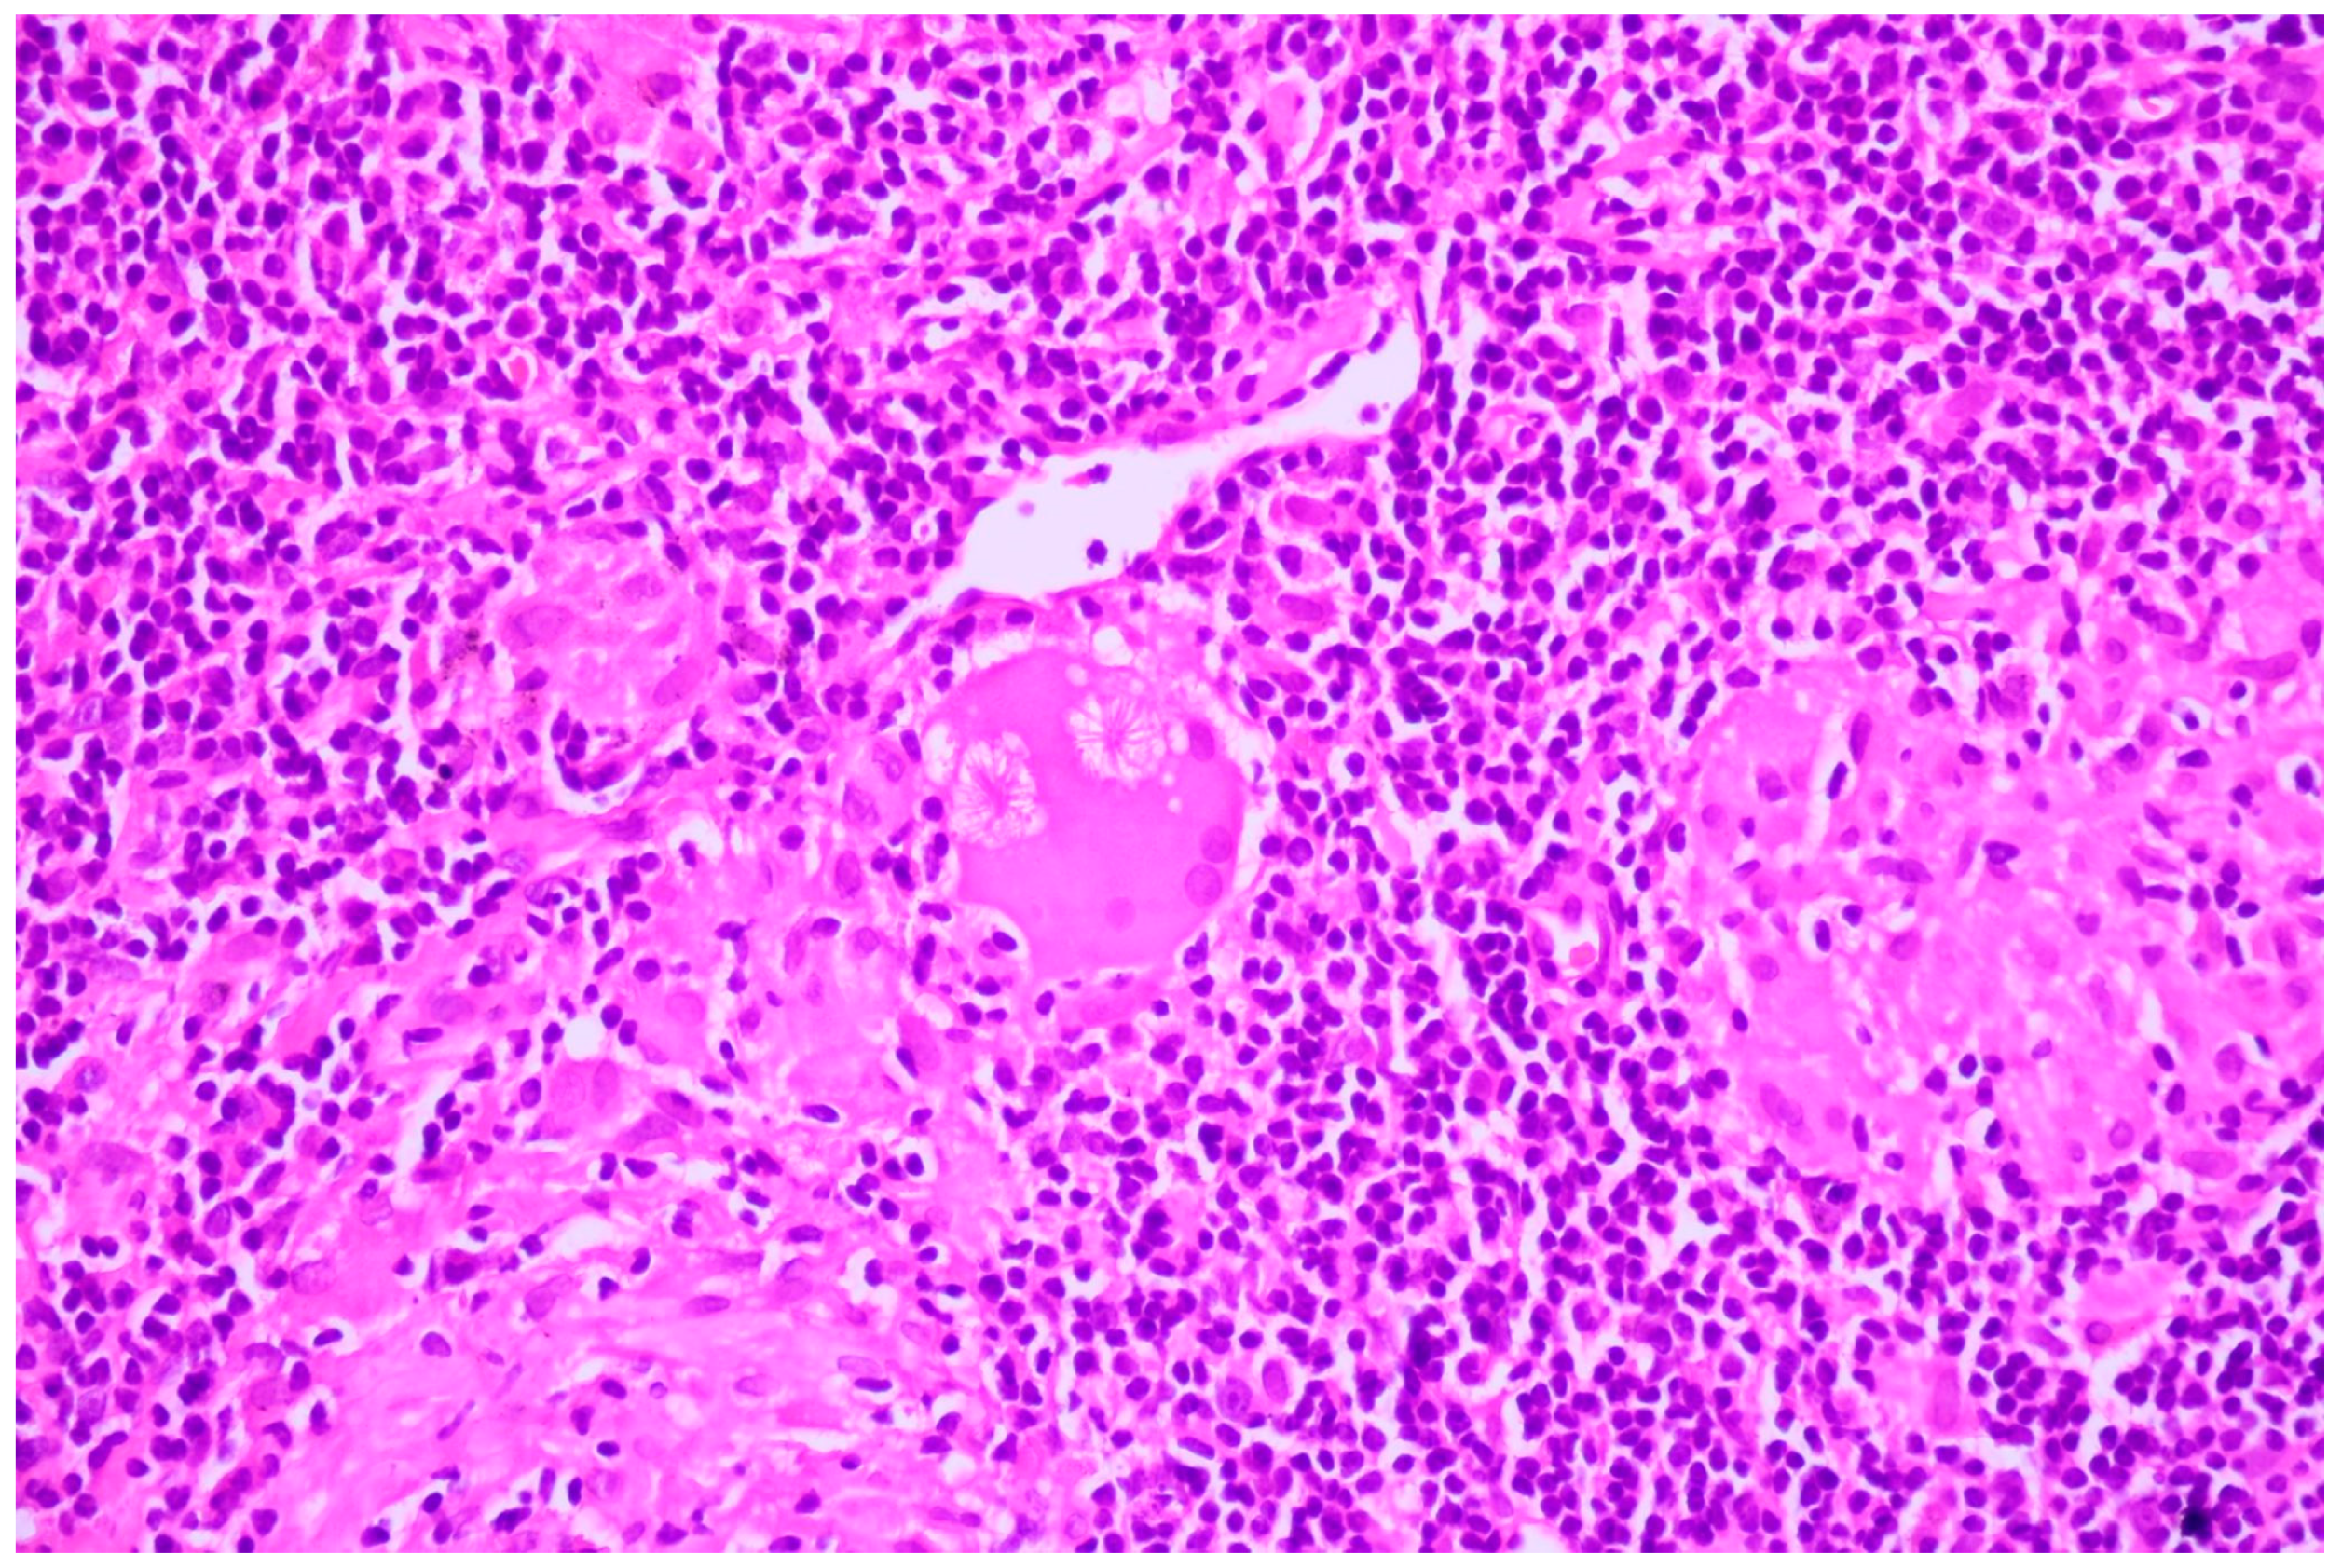

Sarcoidosis is characterized by the presence of well-defined, compact, non-necrotizing granulomas primarily localized within the interstitium and excluding airspaces [16]. These granulomas are frequently observed in anatomical structures such as the pleura, interlobular septa, and broncho-vascular bundles, typically following lymphatic routes [16]. While a thin rim of chronic inflammation may surround these granulomas, it generally does not extend into the adjacent interstitium [16]. Although granulomas may occasionally contain small areas of central necrosis, such occurrences are typically inconspicuous [16]. Furthermore, these granulomas may harbor common multinucleated giant cells exhibiting various inclusions, including Schaumann or asteroid bodies (Figure 11) [16].

Figure 11.

Asteroid bodies in sarcoidosis; HE, 400×.

In the nine cases of NSCLC associated with granulomatous lesions, five of them were represented by active tuberculosis (Figure 2) and four by sarcoidosis (Figure 3).

Figure 3.

Sarcoidosis—well-formed noncaseating epithelioid granulomas; HE, 40×.